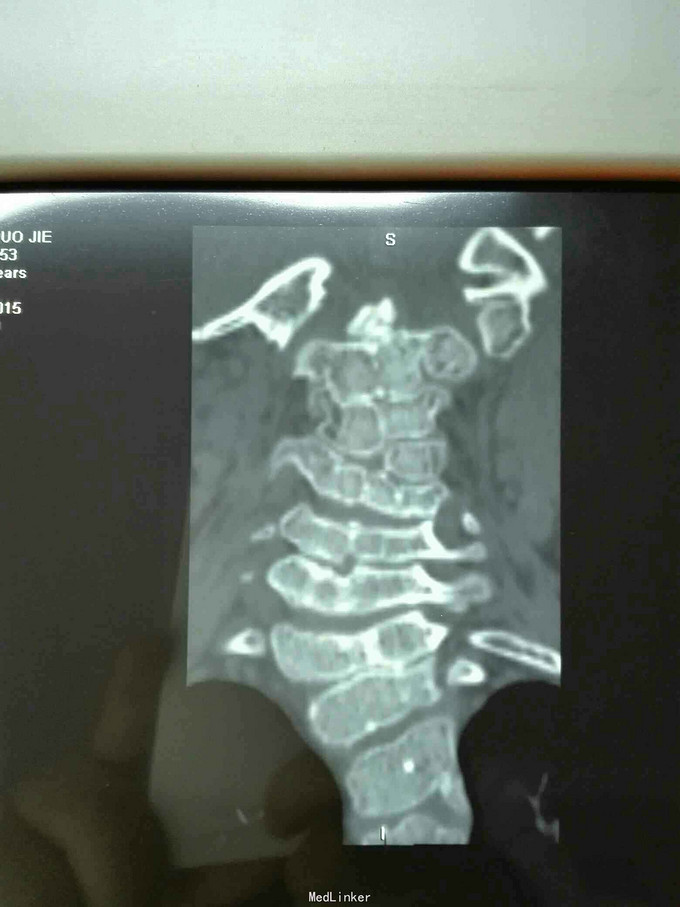

先天脊柱畸形

先天脊柱畸形8年。

严重脊柱畸形病例

先天性脊柱侧凸畸形

脊柱先天畸形